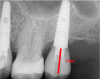

Fig 2. If the distance is less than 7 mm, an unsightly gray dot may result.

Figure 2

The author teaches "restorative address 73-422," a metaphorical street address, as the best method to help navigate an implant start to finish, where each number corresponds to a significant measurement. These measurements can be viewed by looking at the cross-section of a cone-beam computed tomography (CBCT) scan. The first number in the address, "7," represents the distance that the restorative platform should be from the desired occlusal table (Figure 1). An abutment 5 mm in length will minimize the chances of the restoration dislodging from the abutment. Then, above coronal to the abutment, there should be 2 mm of restorative material to ensure a strong restoration that will not fracture or break. Together, the abutment length of 5 mm plus the 2 mm of restorative material equals 7 mm. If the distance between the restorative platform of the implant abutment and the desired occlusal table is less than 7 mm, it will be difficult to mask out the screw-access hole and may result in an unsightly gray dot in the middle of the implant restoration (Figure 2). If the distance is slightly greater than 7 mm, that is acceptable, but it should not be less.